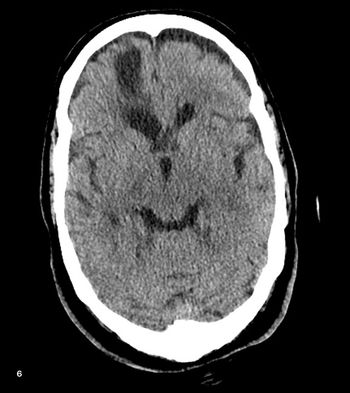

Case History: 12-year-old female presented with fever, altered sensorium, and seizures over a six week period.